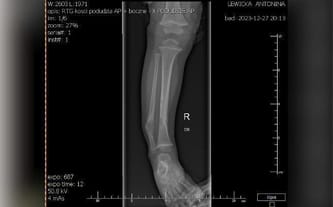

z całego serca dziękujemy za ogromne wsparcie, jakie okazaliście Antosi podczas zbiórki na operację wszczepienia gwoździ śródszpikowych. Dzięki Waszej pomocy udało się przeprowadzić tę skomplikowaną operację, która zakończyła się sukcesem!

Chociaż ten etap leczenia zakończył się pozytywnie, ze względu na naturalny wzrost Antosi w przyszłości będą konieczne kolejne operacje wymiany śrub. Wiemy, że z takim wsparciem, jakie okazaliście, Antosia poradzi sobie z każdym wyzwaniem.